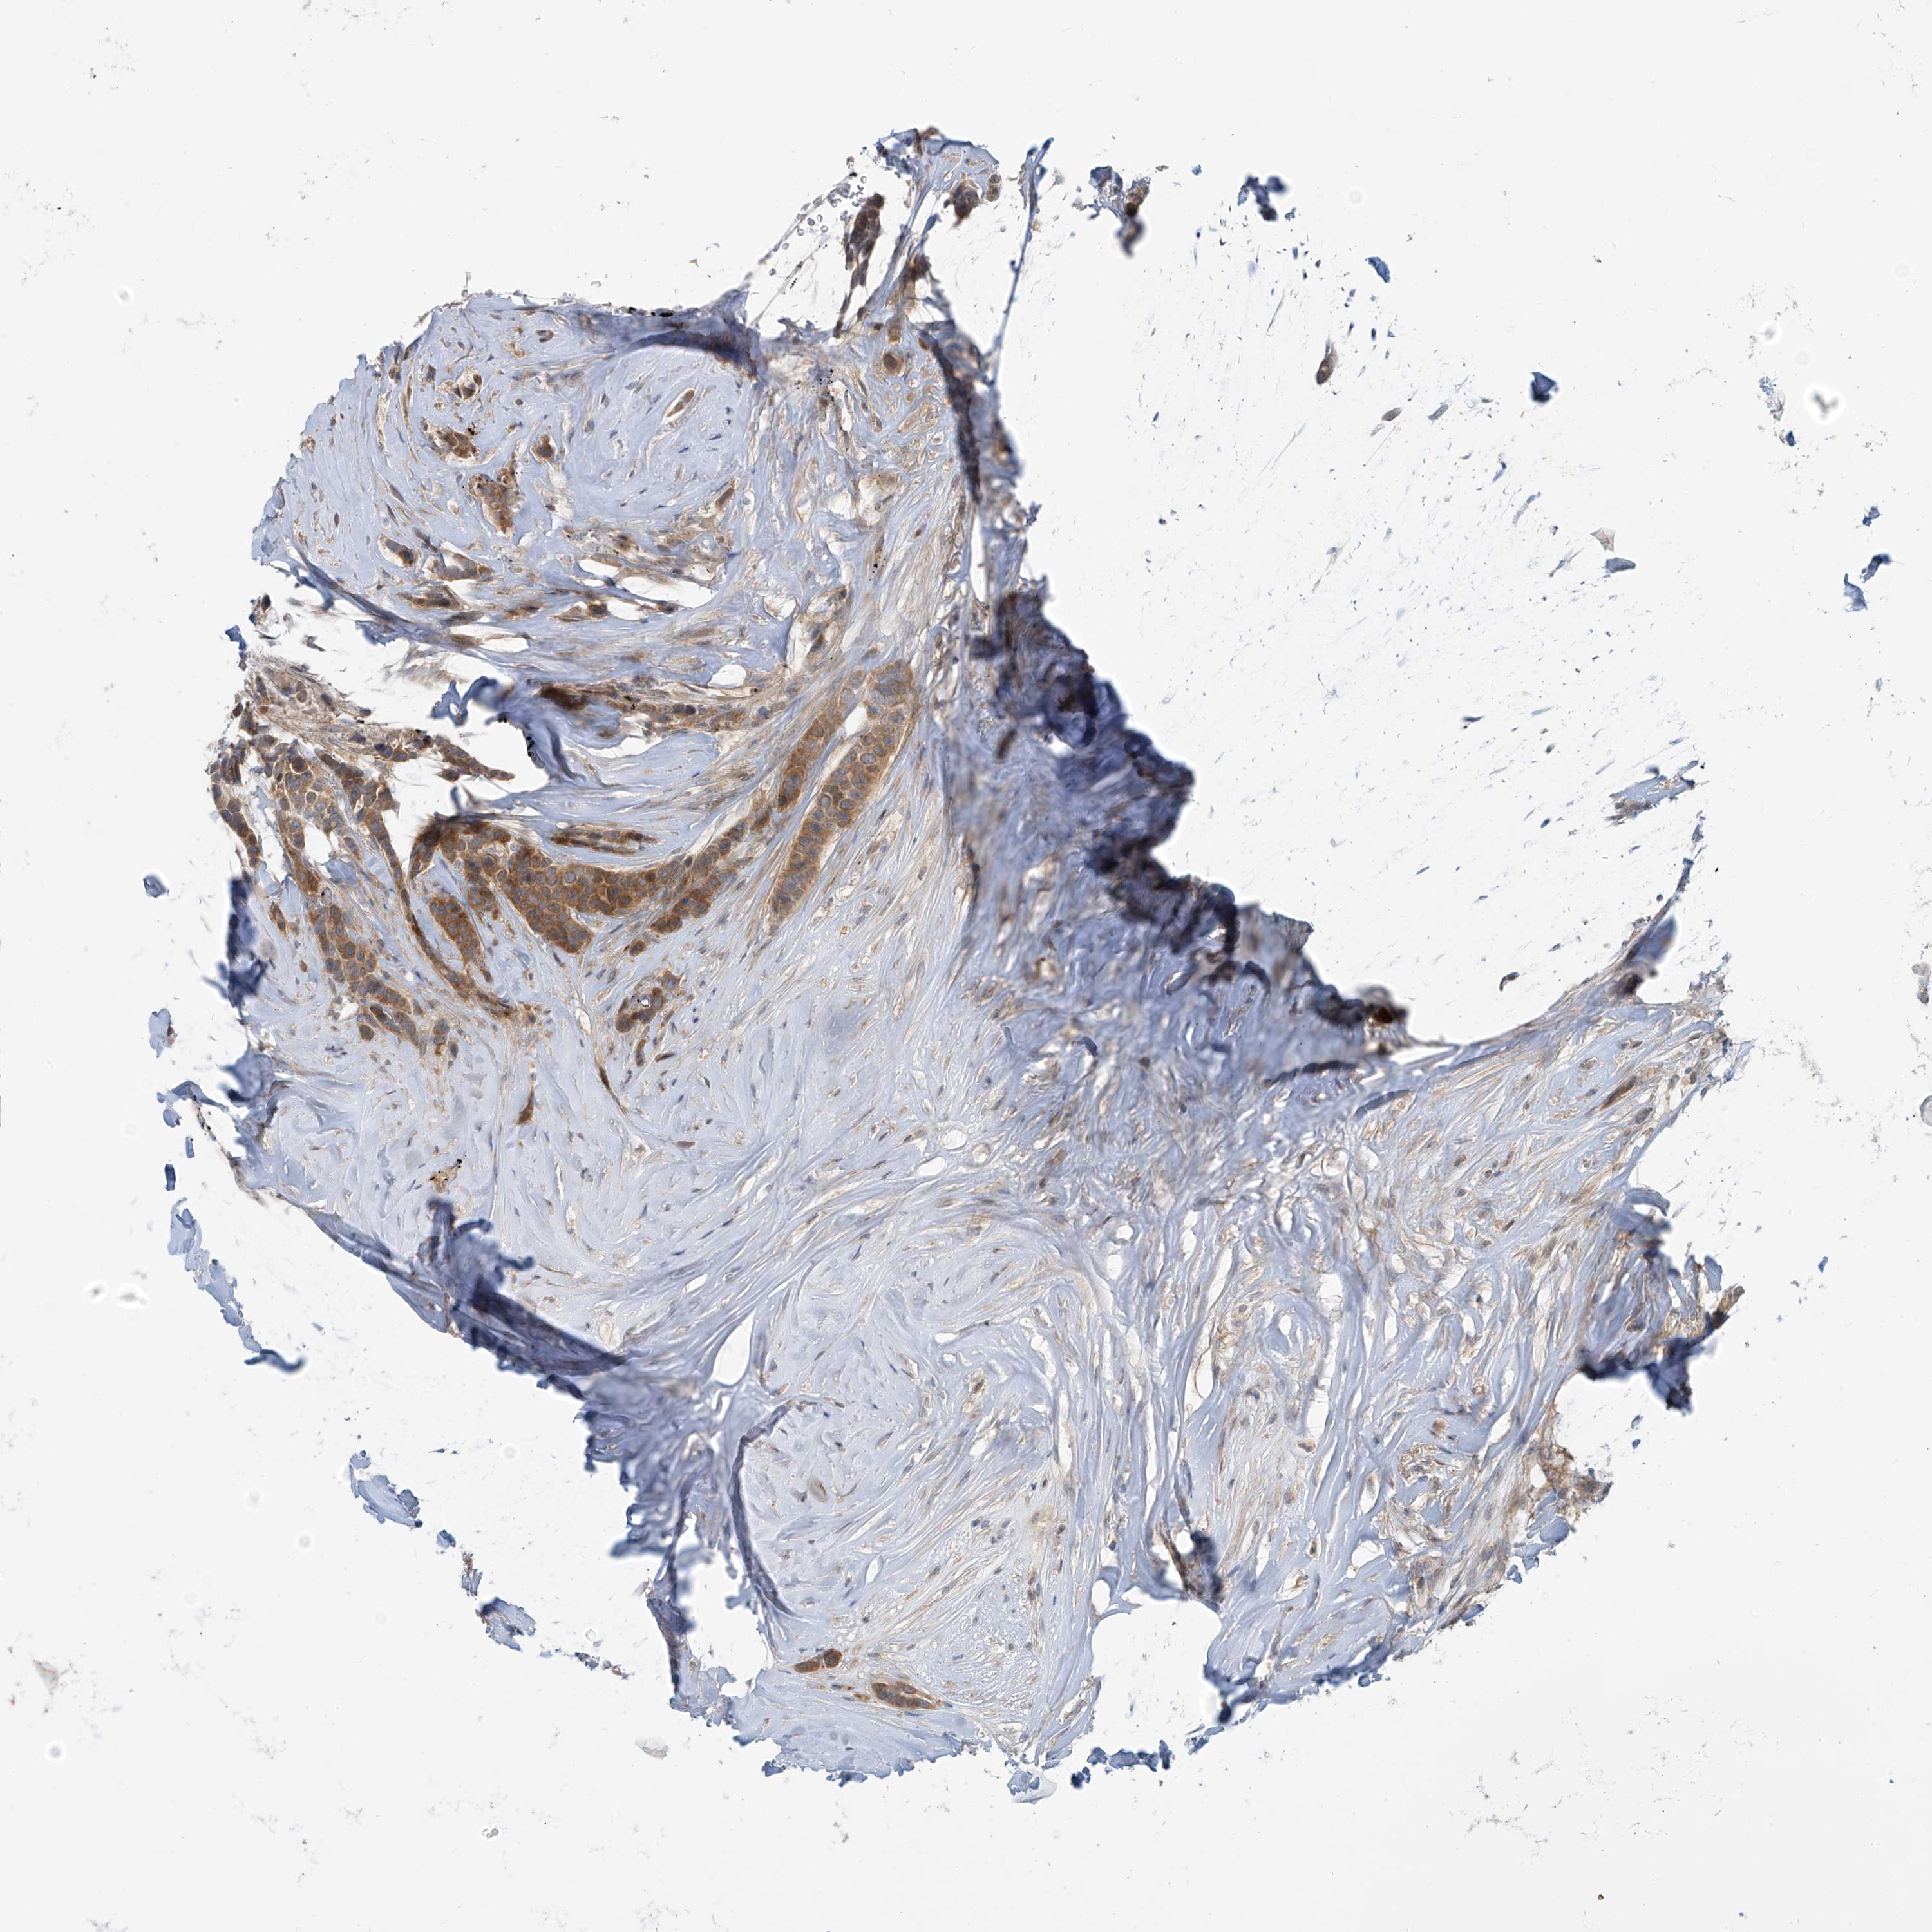

BRCA TCGA BRCA VALIDATION PROTEIN EXPRESSION

Breast cancer

Human cancer